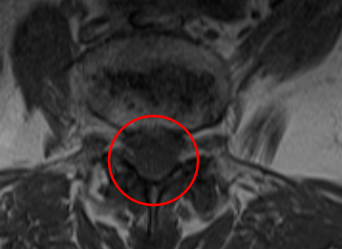

治療後

PEL実施から2週間経過したときには、お尻の痛み、痺れが軽減したとのことです。また治療から4ヶ月後には手術前の痛みと比べて、10から3へ、しびれは10から1になりました(※)。術後のMRIでも狭窄症の圧迫はきれいにとれていました。